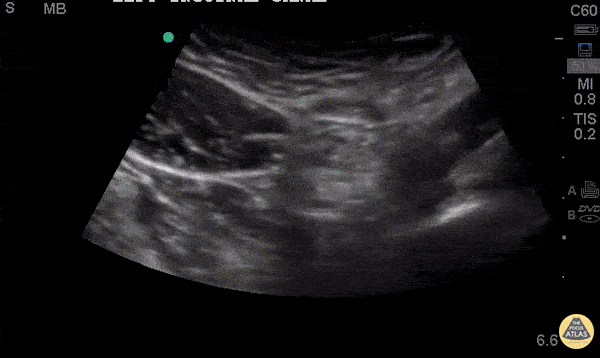

33 y/o M p/w LLQ and groin pain since bending and lifting heavy boxes the day before. Clinically appears to have an inguinal hernia. Using the inguinal ligament as a guide, the inguinal canal is found at the midpoint between the ASIS and pubic symphysis, just superior to the ligament. The epigastric vessels mark the deep opening of the canal. This can help determine an indirect from direct inguinal hernia. It is estimated that the sensitivity and specificity of POCUS for inguinal hernia detection are 97% and 87% respectively. PMID: 12831490 This is a transverse cut across the left inguinal canal. As the probe moves downward toward the left scrotum, you can see a small loop of bowel contained within the canal. To confirm this is bowel, peristalsis can be seen with fecal material moving in the lumen. There does not appear to be hyperemia or free fluid indicating incarceration or strangulation. The patient was referred to general surgery for repair. Ronald J. Rivera, PGY3 SUNY Downstate / Kings County Emergency Medicine This is the article I used for the sensitivity and specificity: https://www.ncbi.nlm.nih.gov/pmc/articles/PMC1964363/